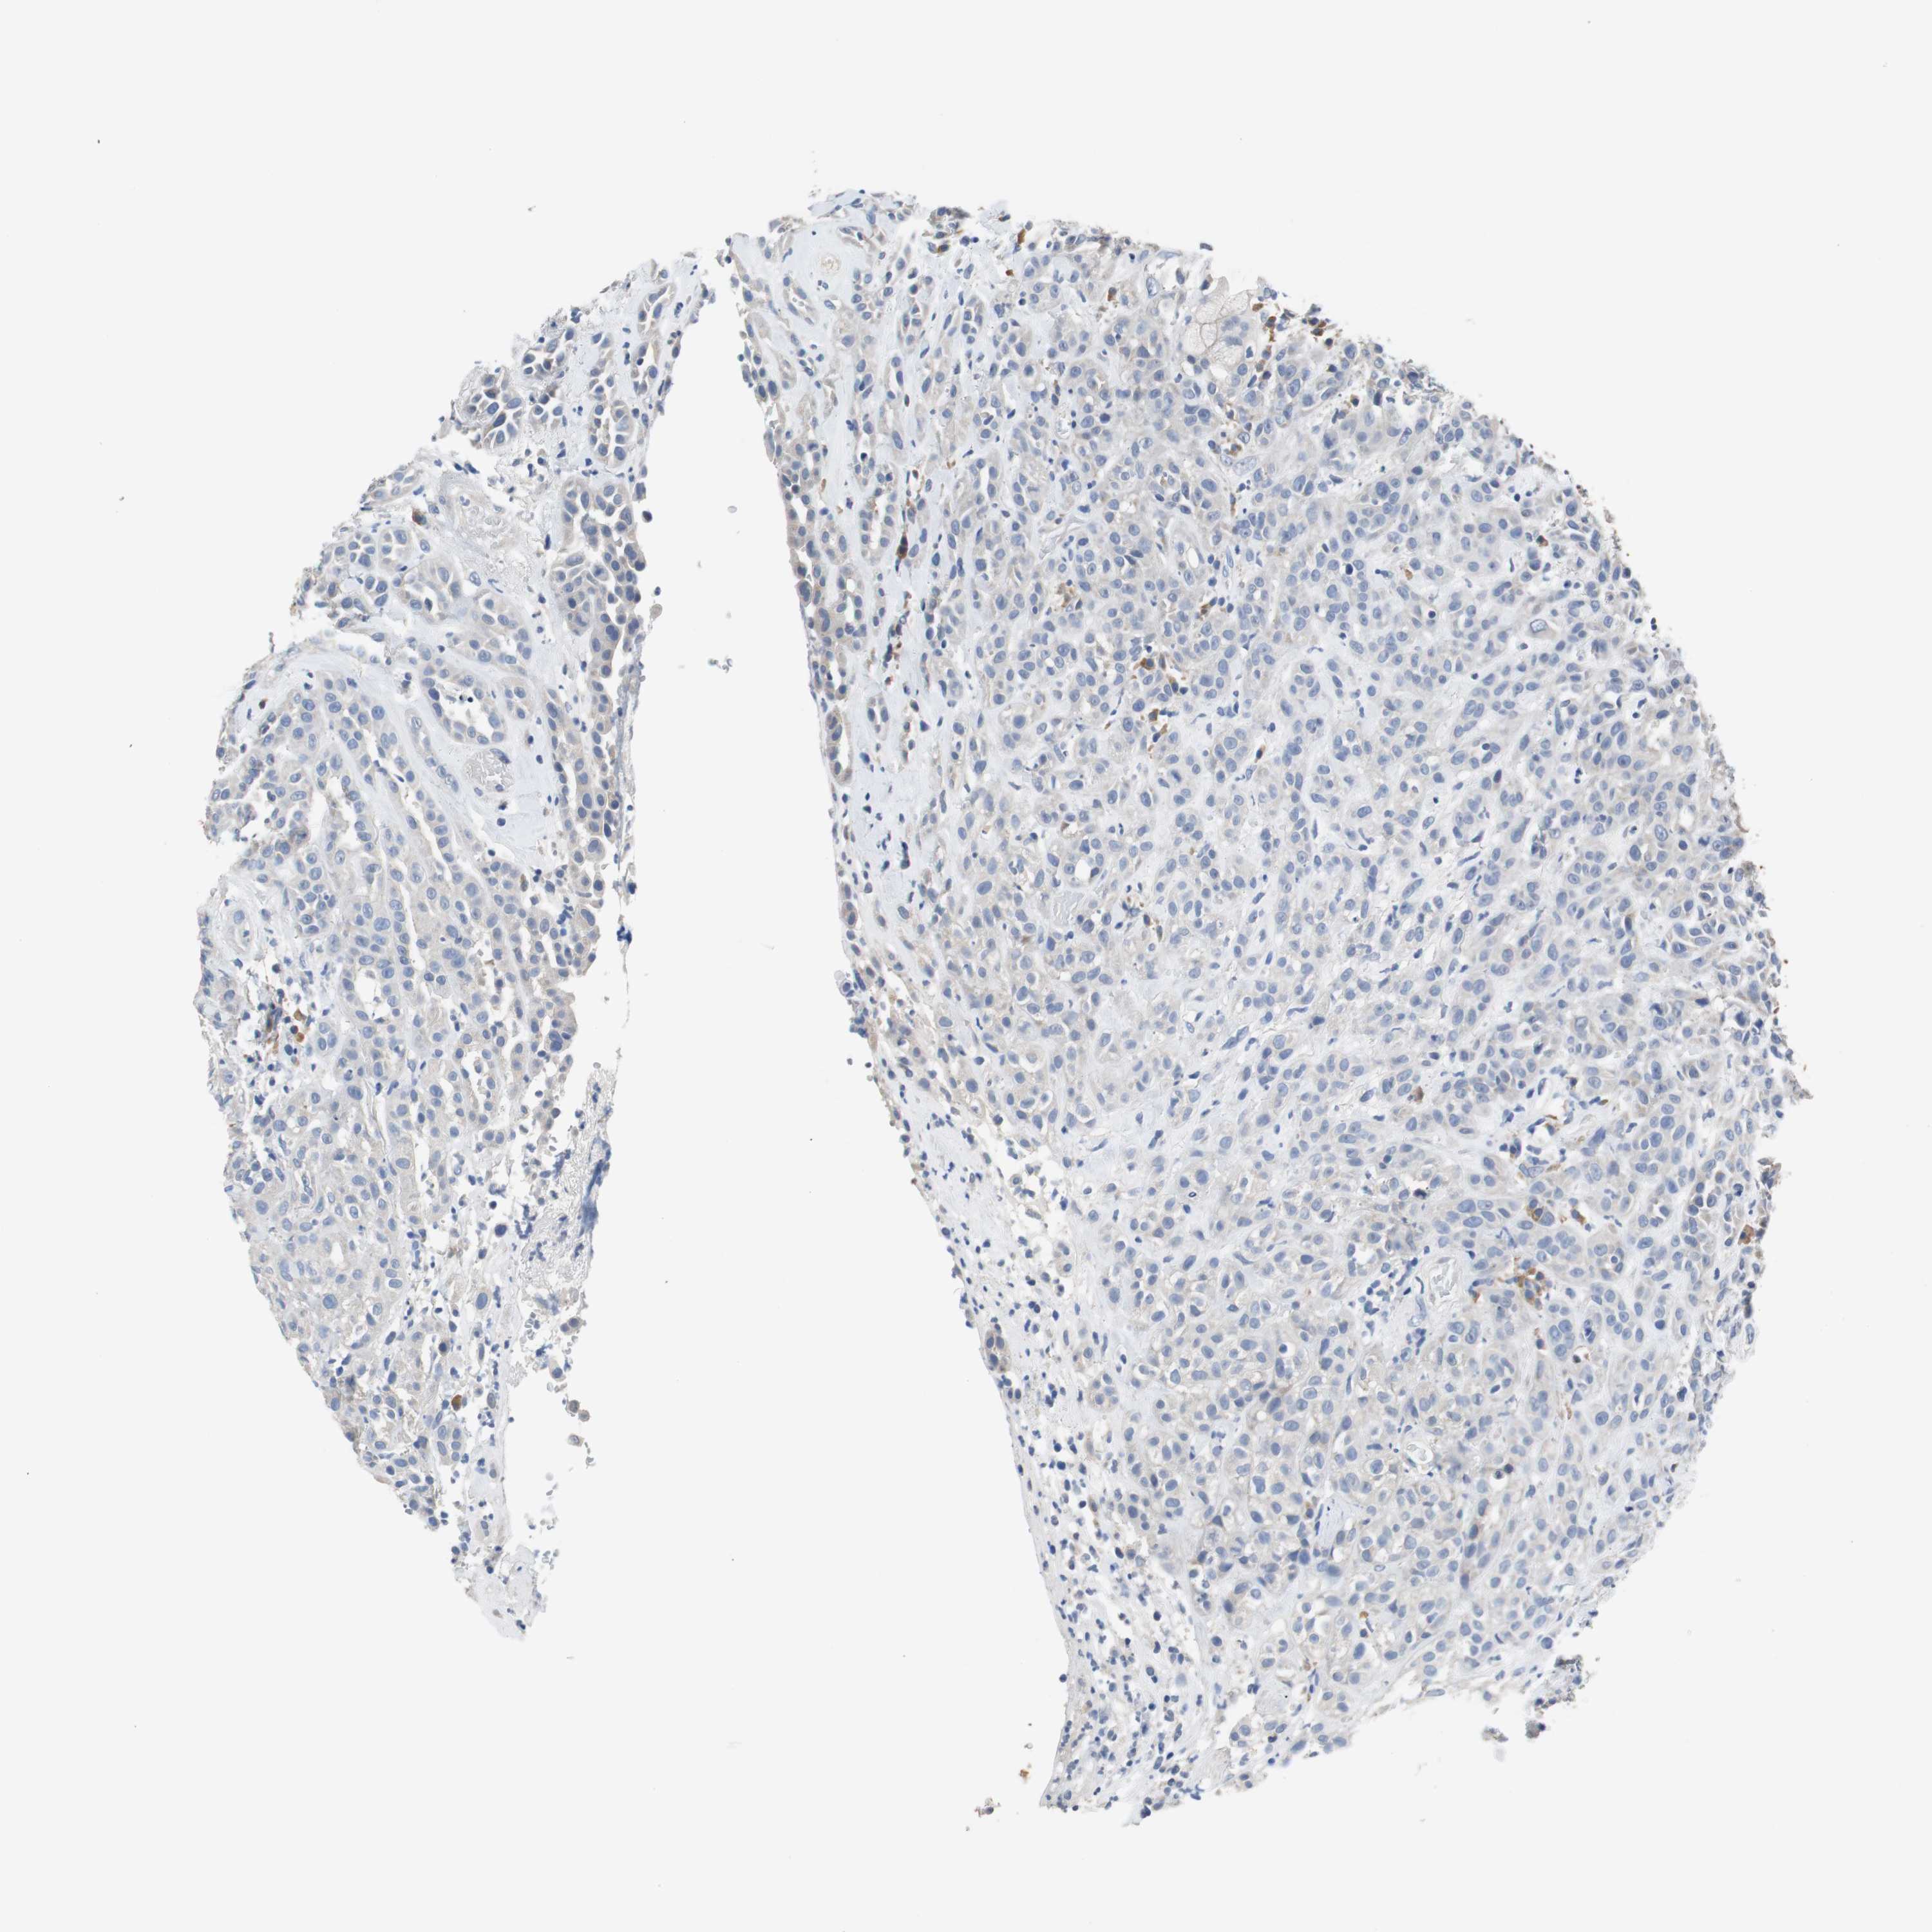

HEAD AND NECK CANCER - Protein expressioni

A mouse-over function shows sample information and annotation data. Click on an image to view it in a full screen mode. Samples can be filtered based on level of antibody staining by selecting one or several of the following categories: high, medium, low and not detected. The assay and annotation is described here.

Antibody stainingi

Antibody staining in the annotated cell types in the current human tissue is reported as not detected, low, medium, or high, based on conventional immunohistochemistry profiling in selected tissues. This score is based on the combination of the staining intensity and fraction of stained cells.

Each image is clickable and will lead to virtual microscopy that enables deeper exploration of all samples and also displays staining intensity scores, fraction scores and subcellular localization as well as patient and tissue information for each sample.

Antibody HPA006277

Antibody HPA006507

Antibody CAB017027

Staining

High

Medium

Low

Not detected

Intensity

Strong

Moderate

Weak

Negative

Quantity

>75%

75%-25%

<25%

None

Location

Nuclear

Cytoplasmic/membranous

Cytoplasmic/membranous,nuclear

Squamous cell carcinoma, NOS

Carcinoma, NOS

Adenocarcinoma, NOS

Squamous cell carcinoma, metastatic, NOS

Adenoma, NOS